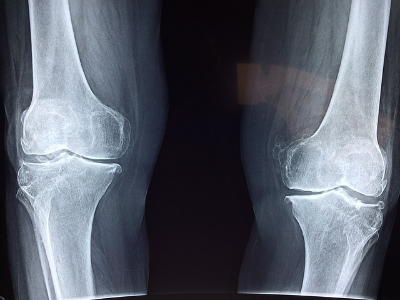

나이가 들수록 관절의 건강은 더욱 중요한 문제이다.

관절염은 평균 55세 이상의 사람들의 움직임을 불편하게 하는 주된 원인이 되기도 한다.